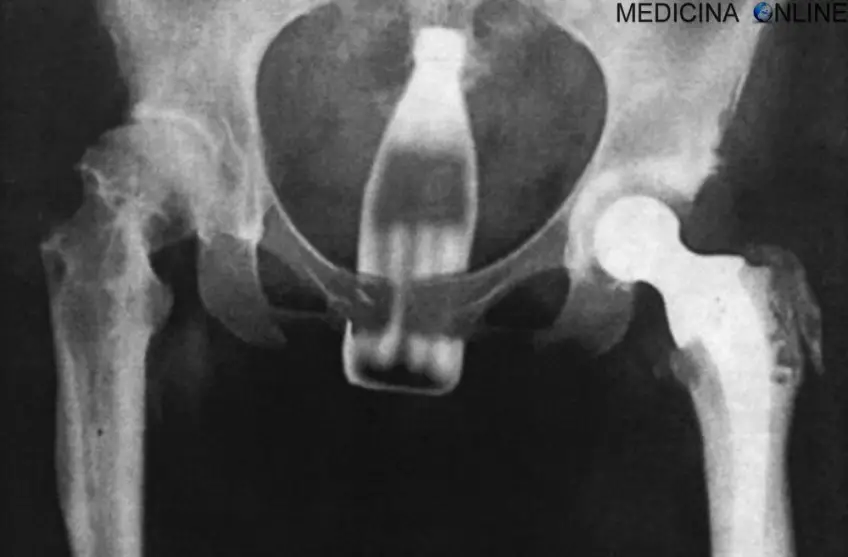

MEDICINA ONLINE OGGETTI CORPO ESTRENEO ANO BAMBINO ESOFAGO STOMACO BATTERIE SEX TOYS OGGETTI SESSO GIOCATTOLI TOSSICI BOTTIGLIA PENNA PENNARELLO COLON RETTO RISCHI COSA FARE COLONSCOPIA

Published 18/04/2018 at 1000 × 657 in Corpi estranei nel tratto digerente: rischi e cosa fare in bambini e adulti

MEDICINA ONLINE OGGETTI CORPO ESTRENEO ANO BAMBINO ESOFAGO STOMACO BATTERIE SEX TOYS OGGETTI SESSO GIOCATTOLI TOSSICI BOTTIGLIA PENNA PENNARELLO COLON RETTO RISCHI COSA FARE COLONSCOPIA INTESTINO DIGERENTE RX RADIOGRAFIA